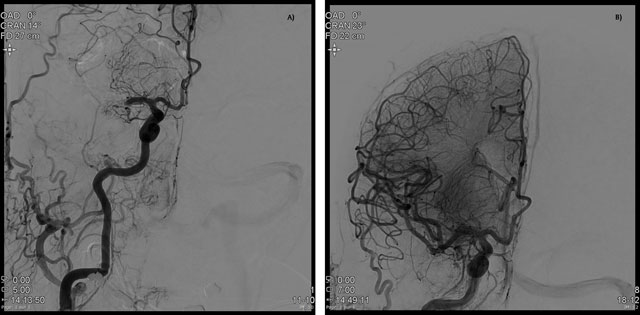

Figure 1

Proximal middle cerebral artery occlusion on catheter angiography (A). Optimal patency restauration after thrombectomy (B).